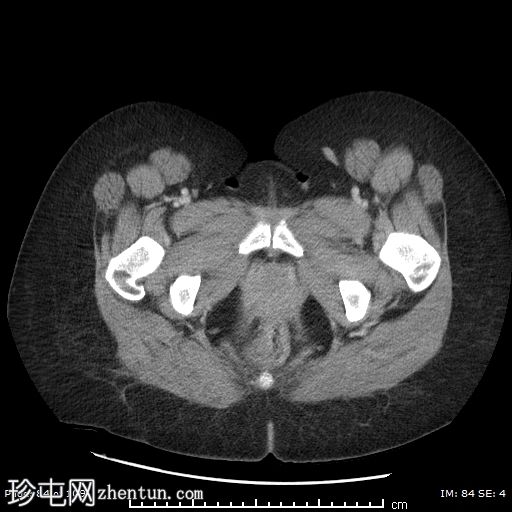

冠状位平扫

矢状位平扫

左侧附件区可见一巨大囊性病变,大小约9 x 12 cm,主要呈液体密度,囊壁光滑薄。

邻近一复杂囊性成分,向中线延伸,大小约10 x 9 cm,内部可见分隔及不均匀液体密度,提示内容物可能为出血性或部分复杂性。

左侧附件区可见一边界清晰的卵圆形低密度肿块,大小约4 x 4 cm,囊壁厚,内部为软组织、脂肪和液体混合密度,符合成熟囊性畸胎瘤(皮样囊肿)的影像学表现。

左侧附件血管蒂扭转,形成血管和软组织呈漩涡状排列,高度提示卵巢扭转。

可见轻度卵巢周围脂肪条索状改变和少量邻近盆腔积液,可能为继发性充血和水肿。

由于左侧附件增大的组织结构压迫,子宫向右侧移位。